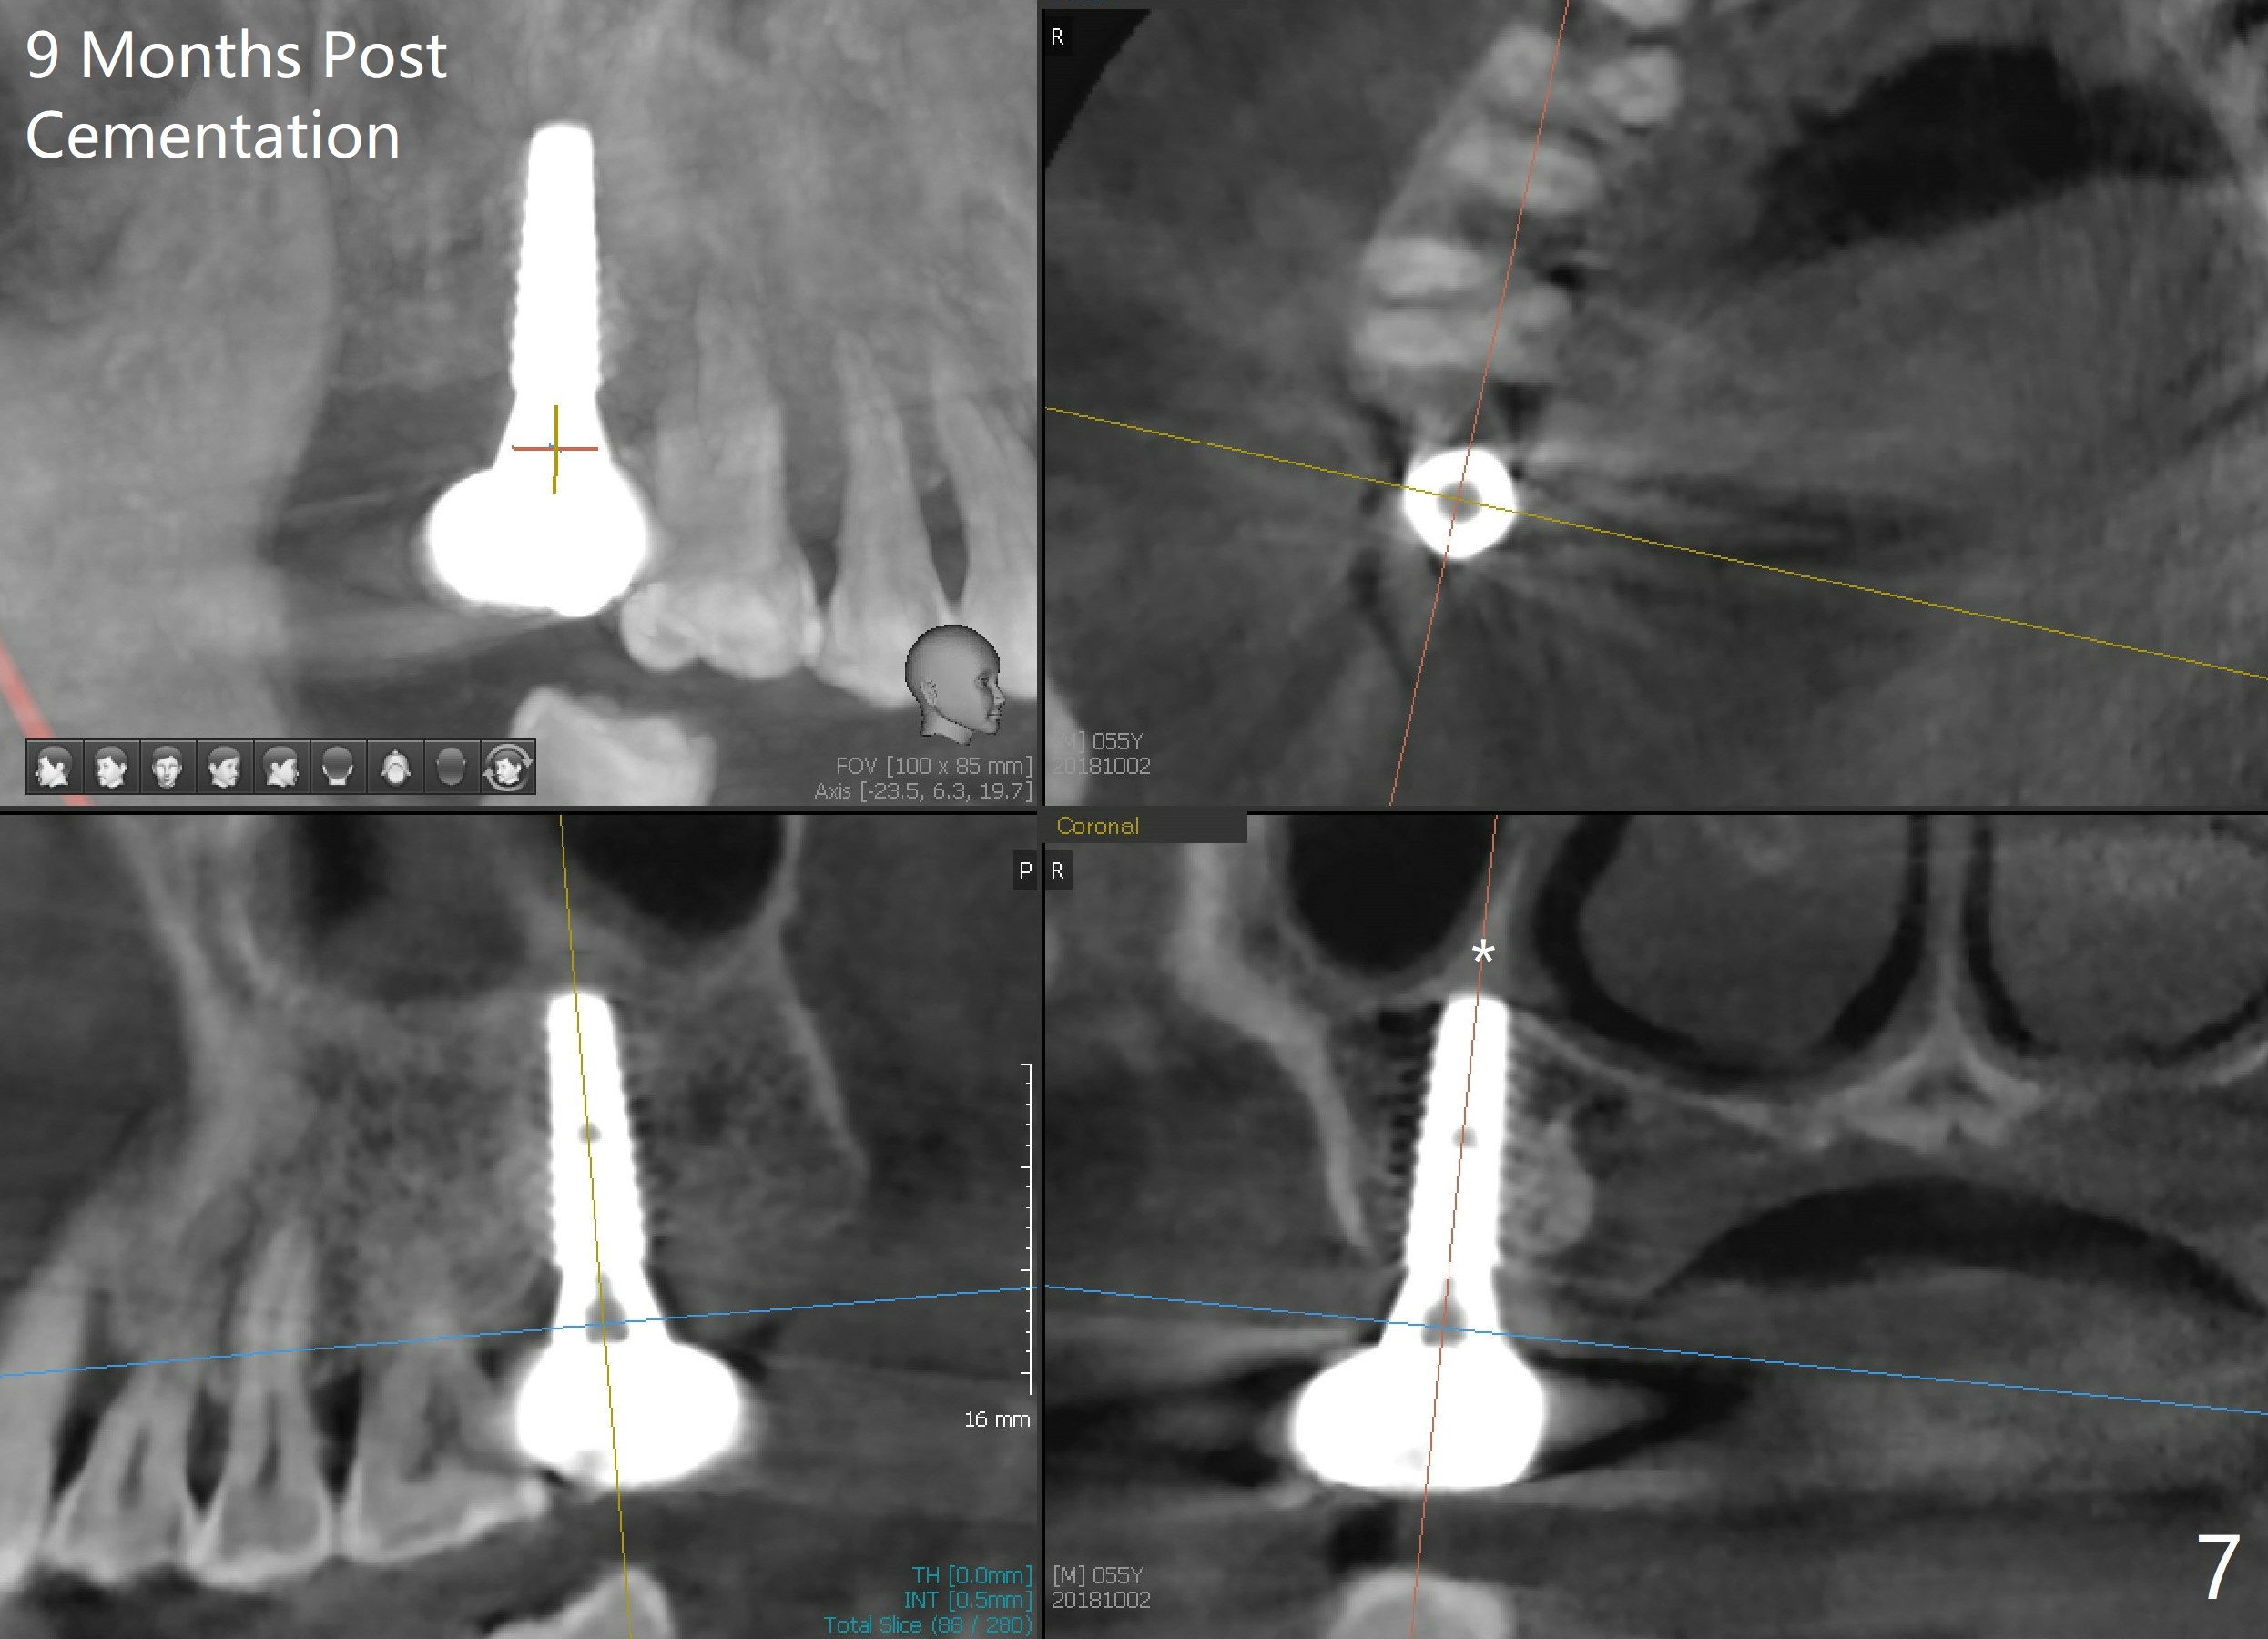

The edentulous ridge at the site of #2 is wide. Magic split is used to gain access, test bone density and start osteotomy for 9 mm (gingival level). A 1.6 mm drill is used to extend the osteotomy for depth of 13 mm. The osteotomy position and trajectory is confirmed with a parallel pin (Fig.1), which is ideal. The remaining osteotomy is finished with Magic Expanders from 3 to 4.3 mm for 15 mm. The trajectory is confirmed again with insertion of a 4.5x11 mm dummy implant at the depth of 15 mm (Fig.2). When a definitive IBS implant (5x13 mm) is placed with insertion torque >45 Ncm, the distal coronal end is not subcrestal (Fig.3-5). As the implant is placed deeper, it started to lose primary stability. When a pair abutment is placed, it keeps turning. Finally a healing abutment (6x3 mm) is placed unstable. In brief, taking several X-ray films help control osteotomy and implant position and trajectory. The implant is unstable 7 months postop (Fig.6). With local anesthesia, the implant is placed deeper by 1 mm with apparent increase in torque and a 6x4 healing abutment placed. The implant is stable 11 months postop. With 5.5x4(4) mm abutment placed, impression is taken. PA and BW will be taken after cementation of the crown. There is no bone loss 9 months post cementation (Fig.7). Return to Upper Molar Immediate Implant, 18-20, 29,30 Xin Wei, DDS, PhD, MS 1st edition 01/09/2017, last revision 08/15/2021